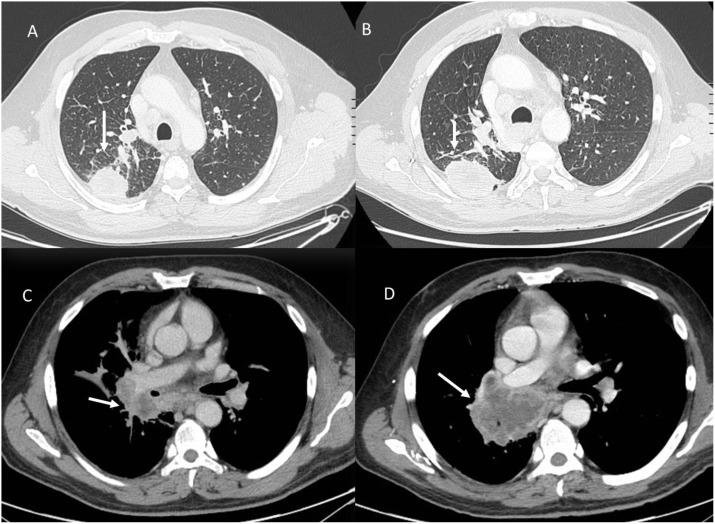

This review highlights the critical role of radiologists in personalized cancer treatment, focusing on the evaluation of treatment outcomes using imaging tools like Computed Tomography (CT), Magnetic Resonance Imaging (MRI), and Ultrasound. Radiologists assess the effectiveness and complications of therapies such as chemotherapy, immunotherapy, and ablative treatments. Understanding treatment mechanisms and consistent imaging protocols are essential for accurate evaluation, especially in managing complex cases like liver cancer. Collaboration between radiologists and oncologists is key to optimizing patient outcomes through precise imaging assessments.

本综述强调了放射科医生在个性化癌症治疗中的关键作用,重点在于使用计算机断层扫描(CT)、磁共振成像(MRI)和超声等成像工具评估治疗效果。放射科医生评估化疗、免疫疗法和消融治疗等疗法的有效性和并发症。了解治疗机制和一致的成像方案对于准确评估至关重要,尤其是在处理肝癌等复杂病例时。放射科医生与肿瘤学家之间的合作是通过精确的成像评估优化患者治疗效果的关键。